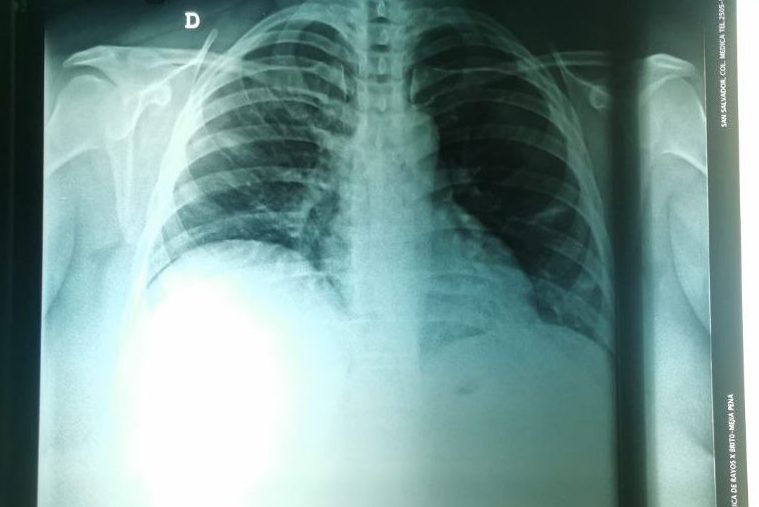

Le mandé la foto de la placa de torax a mi doctora y ya iba en el carro cuando me pone lo siguiente: «hay neumonía, consideramos que amerita ser ingresada para recibir tratamiento por la vena, ya no se puede tratar con medicamentos orales» y acá se me fue el hambre, la vida y las ganas de ser adulta.

Por suerte tengo el seguro de la oficina, hubiera preferido hospitalización en casa pero es extremadamente caro y el seguro no cubre de la misma manera que un hospital. Así que luego de un par de horas de hablarlo con mi familia y con gente de la oficina, decidimos que lo mejor sería venir al hospital, así quye armé una maletita para venirme 5 días, olvidé varias cosas, pero acá estoy desde el lunes por la noche. Se supone que estoy mejorando, que mi oxigenación está subiendo y poco a poco voy a mejorar. Me pusieron oxígeno, me pusieron medicina intravenosa y ahi voy ya.